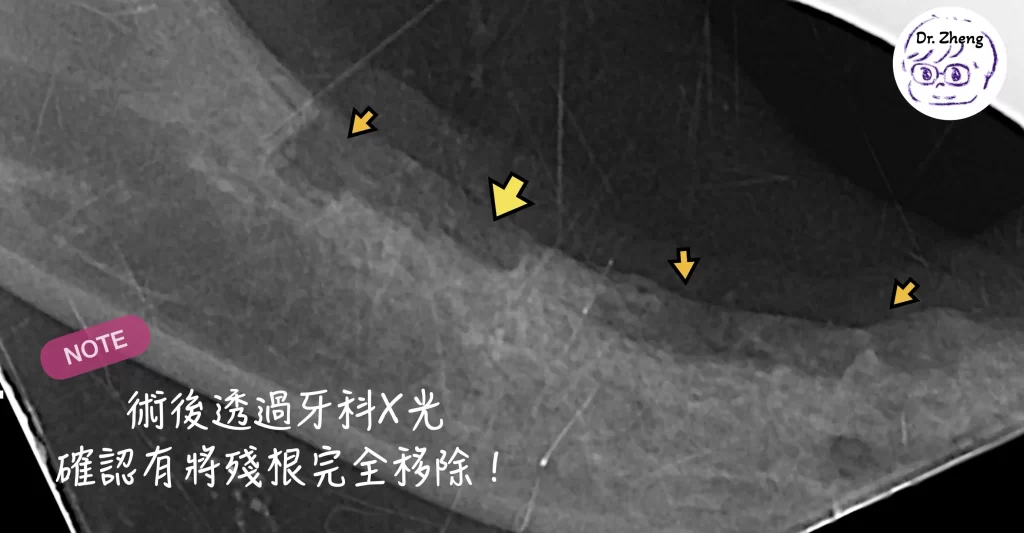

牙科X光檢查發現牙齒殘根

我幫小甜安排了全口牙科X光後發現,原來有4顆齒吸收的牙齒牙冠被拔除,但牙根仍埋在牙齦內未清除!

重點是:要有牙科X光才能正確分類與完整處理。

- 殘根很小,一定要用牙科X光進行診斷和定位